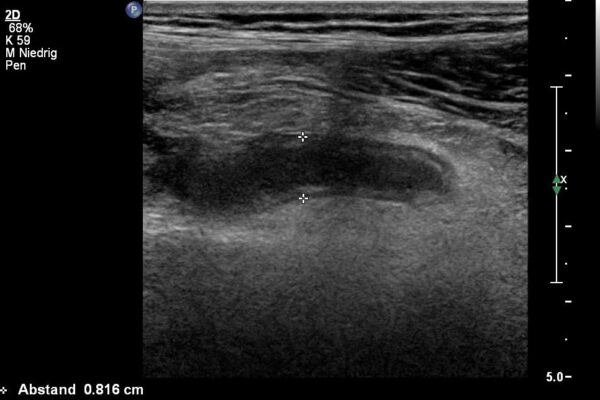

Mit hochauflösenden 18MHz Sonden lassen sich Gelenke, Muskeln, Sehnen und Bänder gut untersuchen.

Die small parts sind eine sehr inhomogene Gruppe von Organen oder Weiteilveränderungen. In dieser Gruppe finden sich oft Untersuchungen der Schilddrüse, der Lymphdrüsen, der weiblichen Brust, der Hoden oder der Haut/Unterhaut.

Häufige Indikationen für Ultraschalluntersuchungen der small parts:

- Haut/Unterhaut: entzündliche Schwellungen, Knötchen (Lipome).